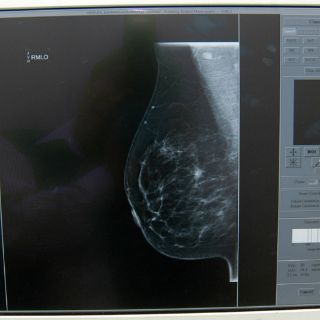

Diseñan dispositivo que detecta cáncer de mama a través de saliva

CIUDAD DE MÉXICO (03/ABR/2016).- La detección del

cáncer de mama en una de sus etapas tempranas favorece su tratamiento, por lo que un equipo del Tecnológico de Monterrey (México) se encuentra desarrollando un dispositivo para facilitar este proceso a través de la saliva.